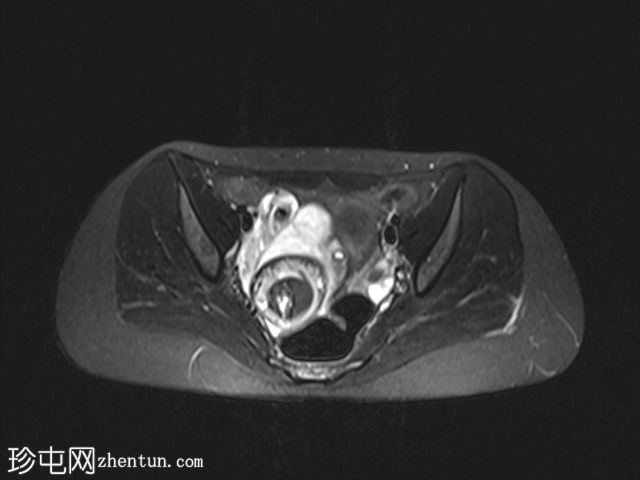

2.jpeg

冠状扫描

非造影扫描

盆腔内可见巨大脂肪密度肿块,伴有牙齿。

右侧附件区可见较大囊性肿块,内含脂肪和液体,大小约为86毫米 x 60毫米。右侧血管蒂扭转,呈漩涡征。右侧卵巢可见增大充血的卵泡,为囊性肿块病变。左侧卵巢正常。